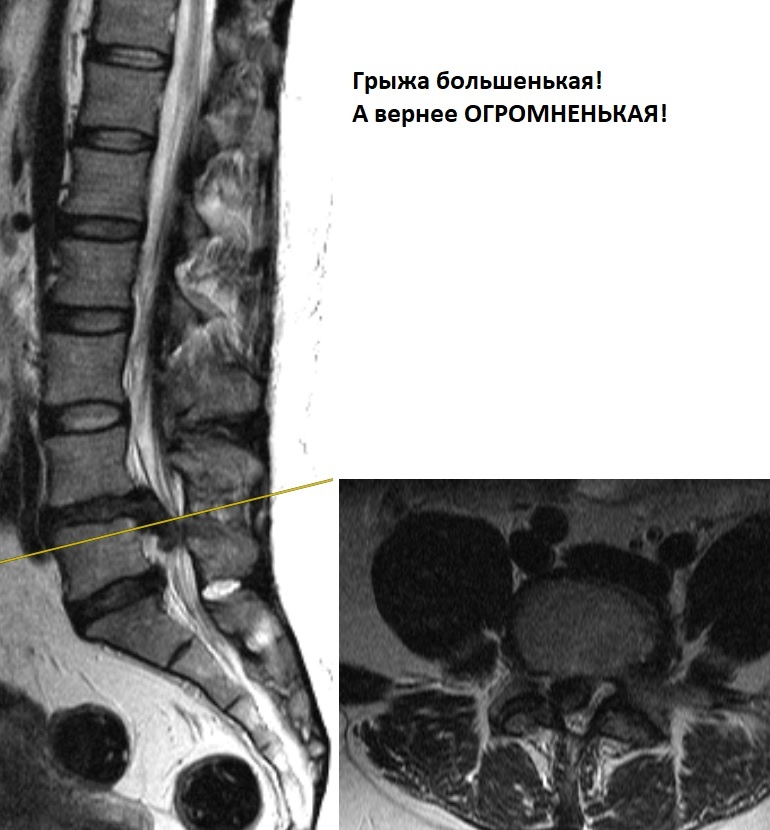

Боооольшая грыжа диска